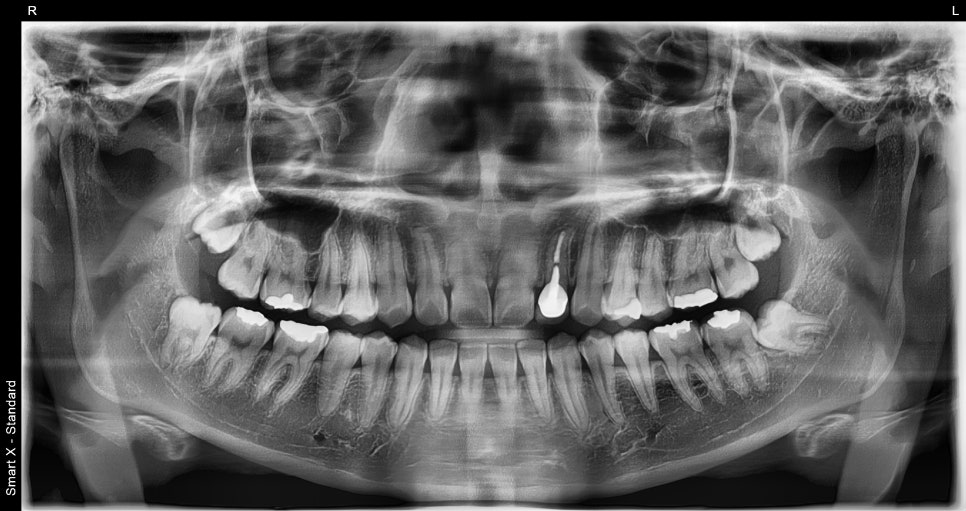

📸 X-ray before extraction

Before extraction, the fully impacted wisdom tooth was buried deep in the bone.